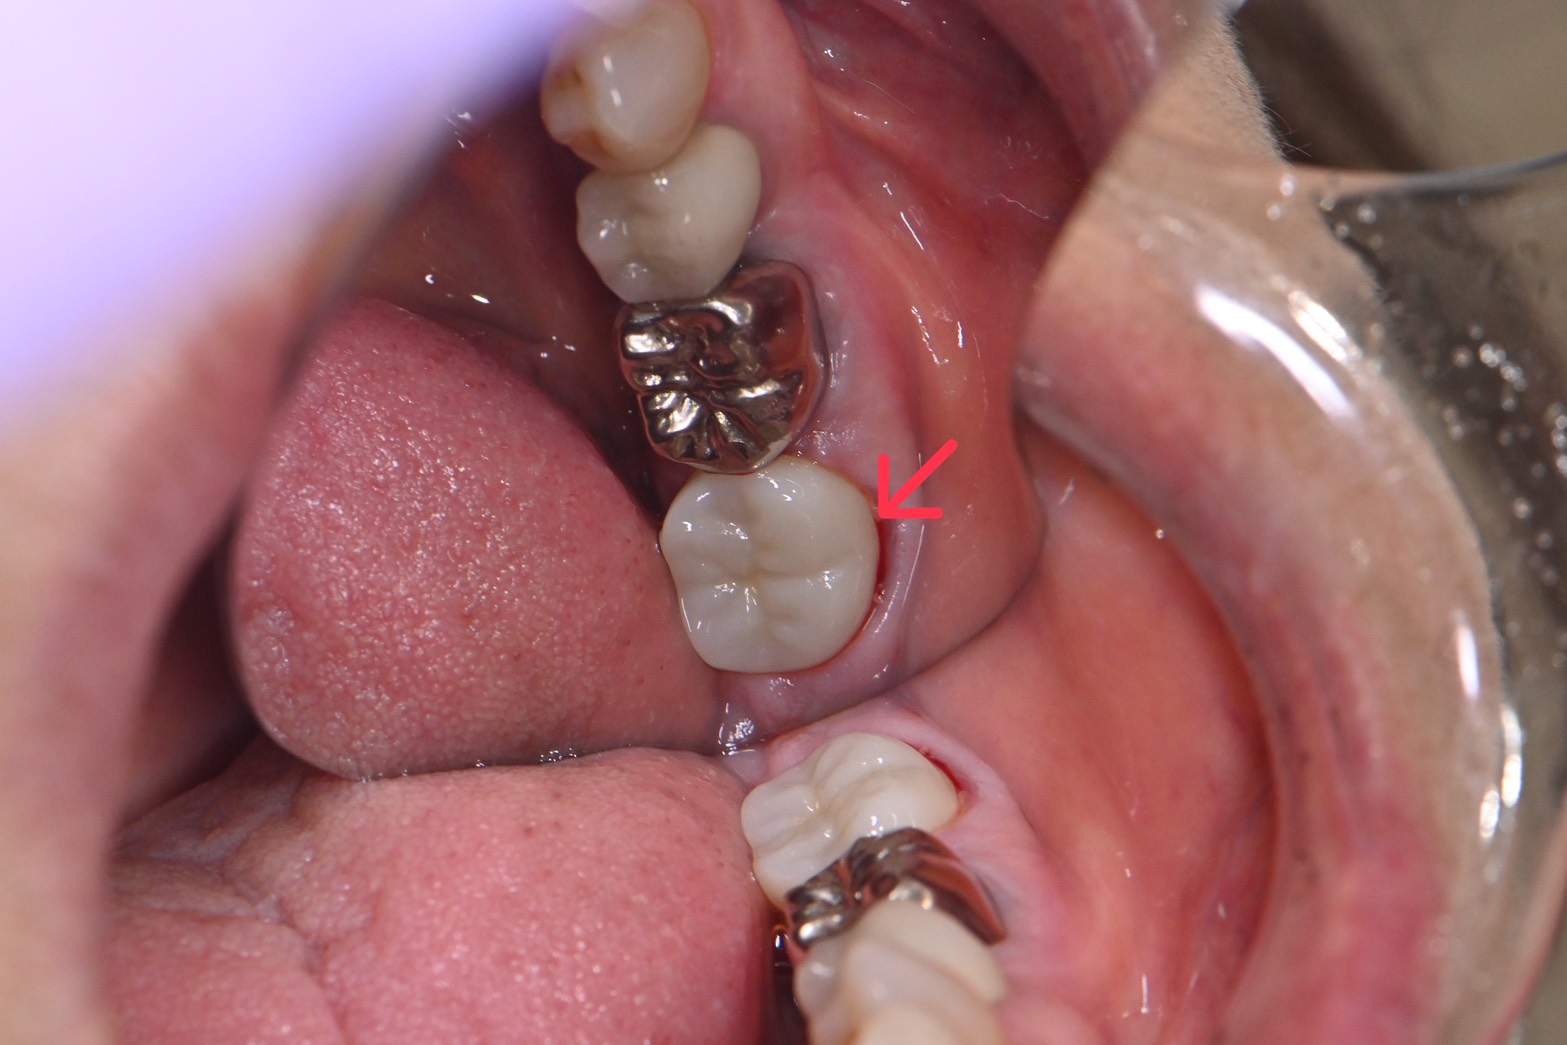

【ジルコニアクラウンをsetした後の写真📸】